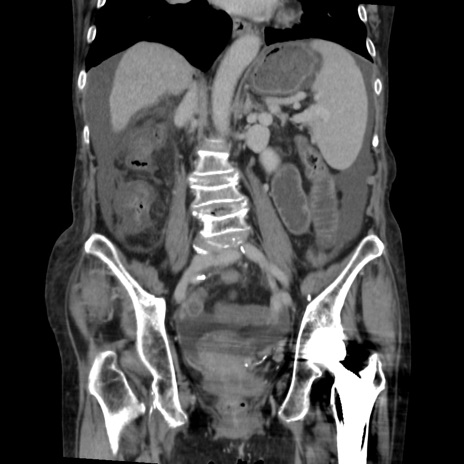

症例31(冠状断像)

【症例】80歳代 女性

【主訴】腹部膨満感

【現病歴】他院にて肝硬変にてフォロー中。1週間前から便秘、腹部膨満感、臍部腫瘤あり受診となる。

【既往歴】肝硬変

【身体所見】腹部膨隆あり、皮膚変化なし、疼痛なし。

【データ】WBC 4600、CRP 0.25